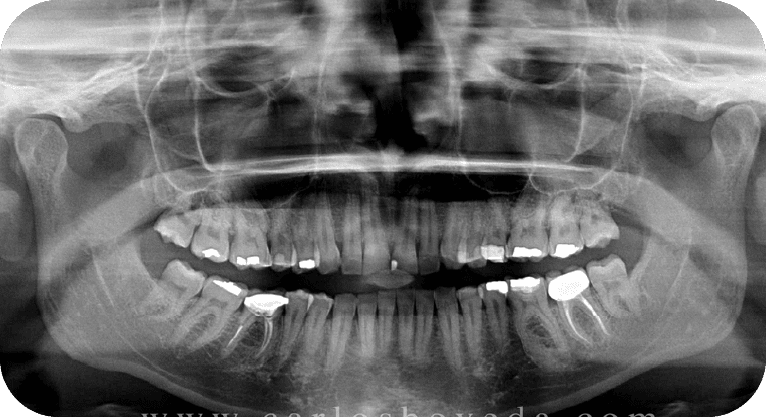

Paciente masculino, “65” años

Tratamiento: Cirugía de encías

El paciente presentaba sensibilidad dental causada por la exposición de los cuellos dentales, por lo que se realizó una cirugía de recubrimiento radicular con injerto gingival y reposicionamiento de encía, logrando

proteger las raíces expuestas, reducir la hipersensibilidad y mejorar tanto la función como la estética periodontal, con resultados satisfactorios para el paciente.

Paciente masculino, “45” años

Tratamiento: Cirugía de encías

El paciente manifestó inconformidad con el aspecto corto de sus dientes, por lo que se realizó una cirugía periodontal de remodelación gingival para recontornear el tejido gingival y exponer mayor superficie dental, logrando así una proporción dentogingival más armónica y mejorando significativamente la estética de su sonrisa.